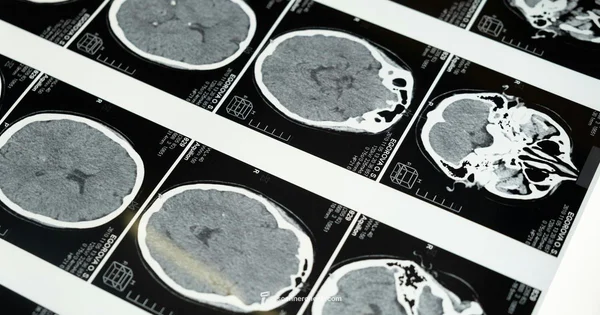

PET scan is a medical imaging technique that uses a radioactive tracer to measure metabolic activity in body tissues, helping identify disease and guide treatment. It is a type of nuclear medicine scan.

A PET scan, or positron emission tomography, is a medical imaging method that uses a radioactive tracer to assess metabolic activity in tissues. If you're wondering what pet scan is, the short answer is that it reveals how your cells are using energy, not just what they look like on anatomy. In practice, a small amount of tracer is injected into a vein and travels through the body. The tracer accumulates in areas with high metabolic activity, such as cancer cells or inflamed tissue. A specialized detector measures the emitted positrons and creates color-coded images that show functional information about tissues and organs. PET scans are often combined with CT or MRI to provide both metabolic and precise anatomical information, making it easier for clinicians to locate problems and plan treatments. This integration is a standard approach in oncology, neurology, and cardiology.